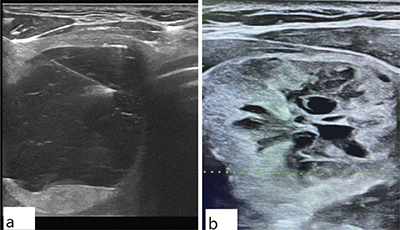

Figure 1

Ultrasound images of thyroid nodules with different categorizations.

(a) This image depicts a nodule with cystic features, characterized by smooth margins and floating colloid, along with echogenic foci and debris (TI-RADS 1). The fine-needle aspiration cytology (FNAC) results for this nodule indicated a nondiagnostic (ND) outcome.

(b) It exhibits a solid composition, an iso-hypoechoic appearance, a heterogeneous texture, central cystic regions, and a lobulated margin (TI-RADS 4). The FNAC results for this nodule indicated atypia of undetermined significance (AUS).